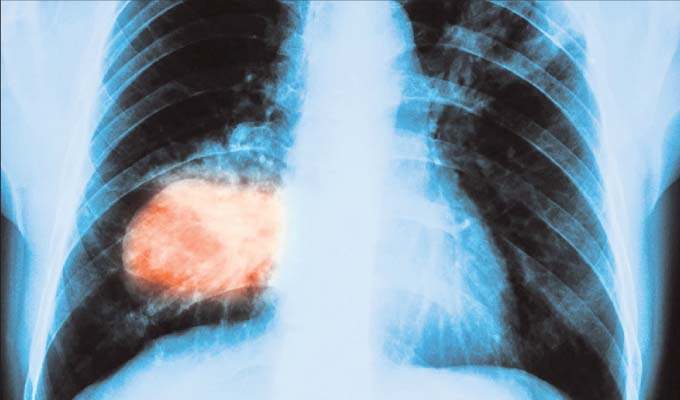

ଧୂମପାନ ଓ ନାରୀ

ଆଜି ବିଶ୍ୱ ତମାଖୁ ବର୍ଜନ ଦିବସ। ଏହି ପରିପ୍ରେକ୍ଷୀରେ ଏହା ନାରୀମାନଙ୍କ ପାଇଁ ମଧ୍ୟ ଗୁରୁତ୍ୱ ବହନ କରେ। କାରଣ କେବଳ ଯିଏ ଧୂମପାନ କରିଥାଏ ସେ ଯେ, ଅସୁସ୍ଥ ହୁଏ ଓ ରୋଗରେ ପଡ଼ିଥାଏ ତାହା ନୁହେଁ, ତାଙ୍କ ଧୂଆଁ…

ତମାଖୁର ଭୟାବହତା

ଧୂମପାନ ହେଉ କି ତମାଖୁ ସେବନର ଭୟାବହତା ବିଷୟରେ ଆମକୁ ଚେତେଇ ଚାଲିବାରେ ଚିକିତ୍ସକମାନେ କୌଣସି ଊଣା କରିନାହାନ୍ତି। ଅଥଚ ଆମ୍ଭମାନଙ୍କ ମଧ୍ୟରୁ ଅନେକେ ଏହି ପରାମର୍ଶକୁ ଏ କାନରେ ଶୁଣି ସେ କାନରେ ବାହାର କରିଦେଉଛନ୍ତି। କାହିଁକି ସେମାନେ ଟାଣି…